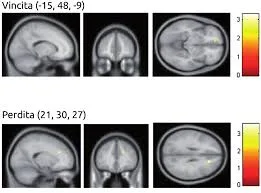

Nella condizione di vincita, i soggetti con IAD si distinguevano per una maggiore attivazione della corteccia orbito frontale rispetto al gruppo di controllo. Nella condizione di perdita, al contrario, nei soggetti dipendenti si registrava una ridotta attività nella corteccia cingolata anteriore.

Fig. 2 – Attivazione cerebrale in condizioni di vincita e perdita in soggetti con dipendenza da Internet. Fonte: Dong G. et al. 2011.

È ampiamente riconosciuto il ruolo della corteccia orbito-frontale nei processi cognitivi e nel creare un’associazione tra comportamento e ricompensa. L’iperattivazione nei soggetti con dipendenza da Internet può essere spiegata da una maggiore sensibilità di questi alla gratificazione, derivante dalla sensazione di controllo e di realizzazione immediata. La ridotta attività nella corteccia cingolata anteriore, invece, è coinvolta nella mediazione delle risposte emotive al dolore. La ridotta attività riscontrata in questa area cerebrale nei soggetti con IAD, può suggerire una minore sensibilità rispetto alle emozioni negative (perdita monetaria, Dong G. et al., 2011).